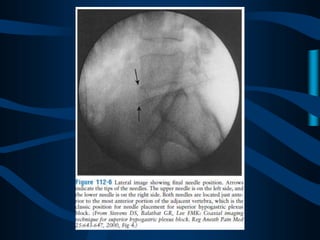

ABORDAJE CLASICO

DE DOS AGUJAS

ABORDAJE

TRANSDISCAL

CON UNA AGUJA